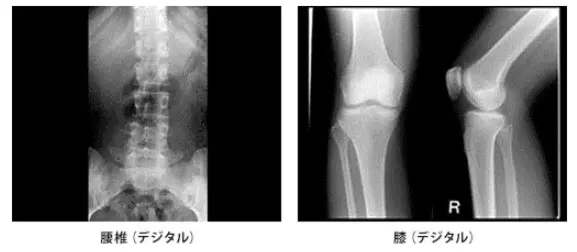

平成23年11月より電子カルテ更新に伴いCRシステム(コニカ製)導入し、フイルムレスで画像診断を行えるようになりました。このシステムは操作性に優れ、フラットパネル採用により、低被ばくで高画質な画像を提供できることができます。

また、検像システム、高鮮鋭度モニターとのシステム化によって高鮮鋭度な画像を配信できるようになり診断の質の向上に寄与しています。